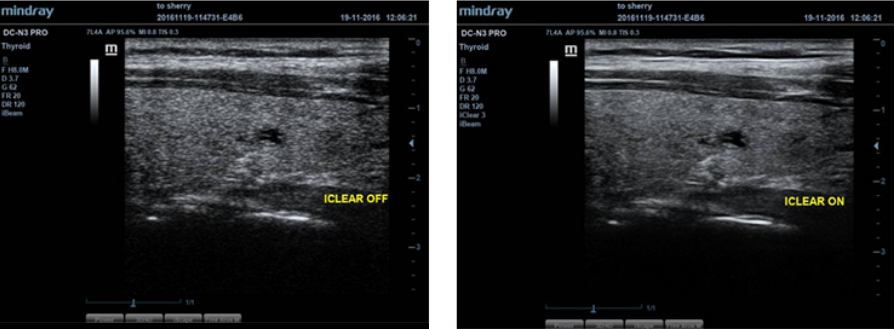

iClear?

?? ?? ?? ???? ??? ?? ?? ??

- ?? ???? ??? ????.

- ???? ??? ??.

- ?? ??? ŌĆś??? ??ŌĆÖ.